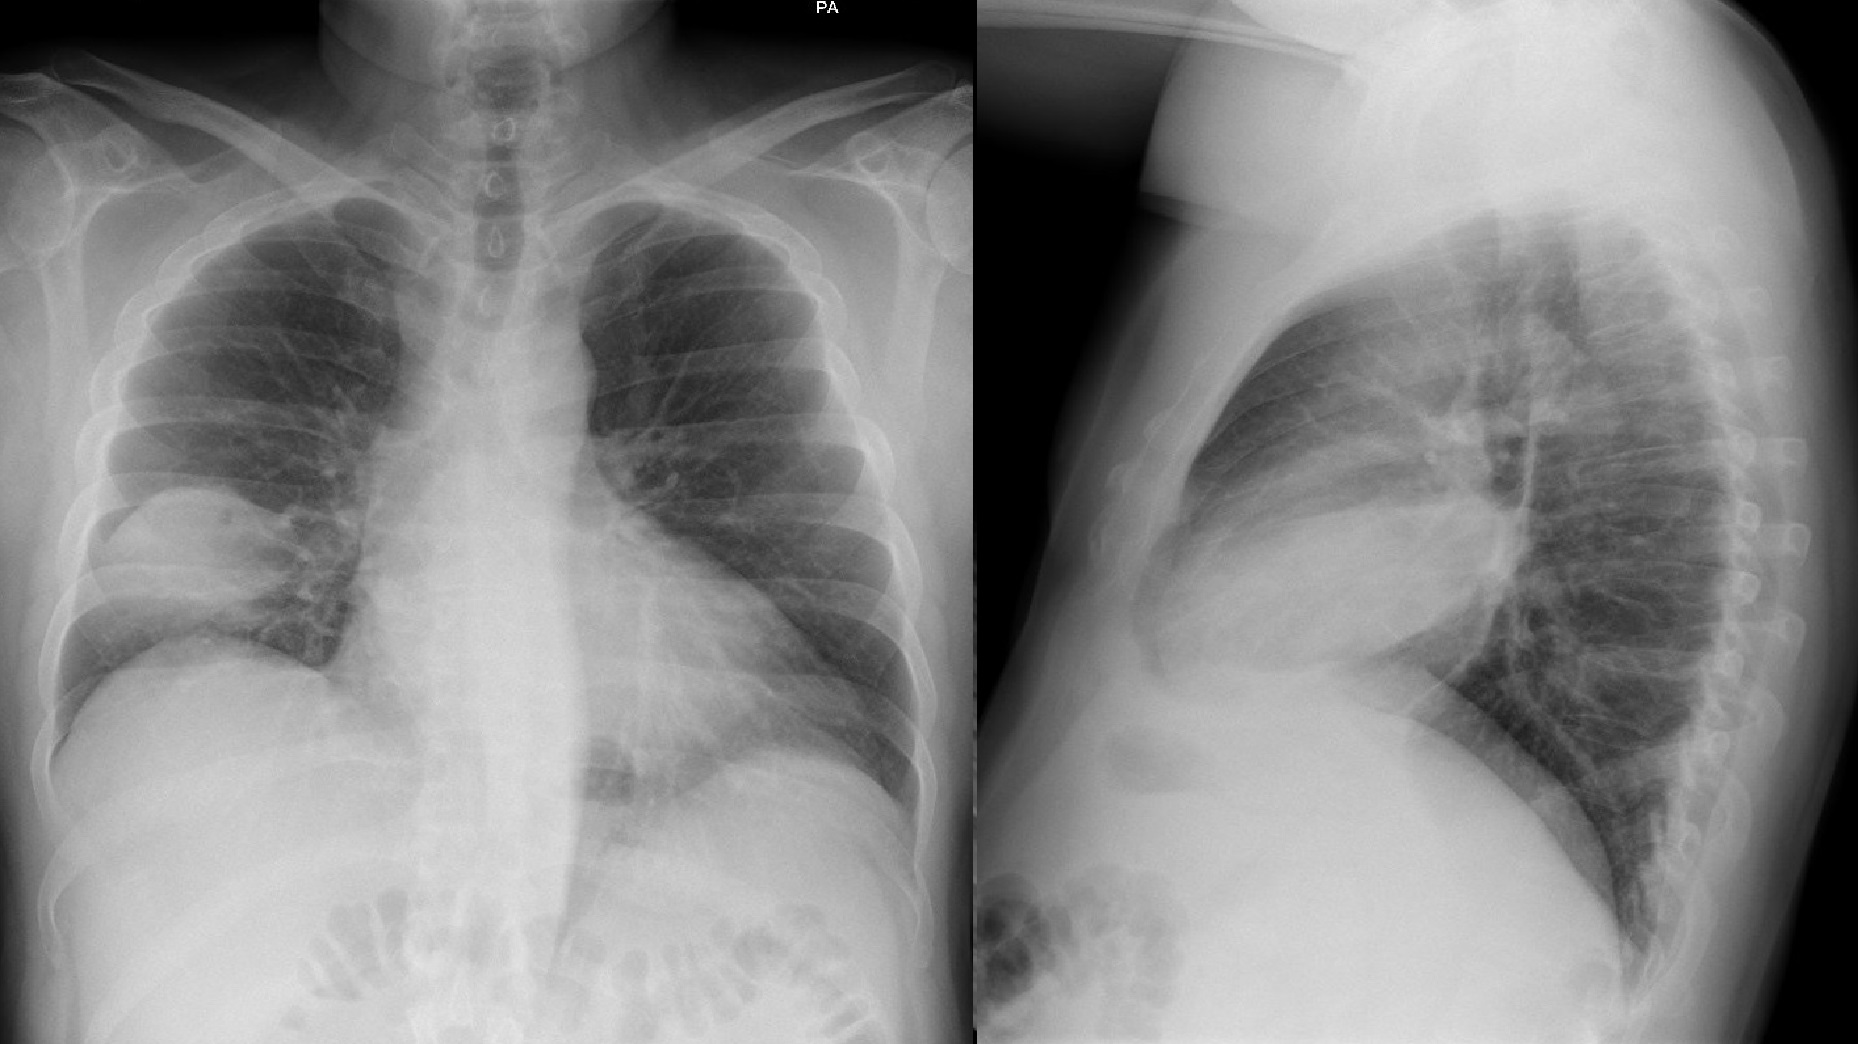

1. Hombre de 56 años sin antecedentes de interés que acude por fiebre de 38 ºC de tres días de evolución con leve disnea, sin otra sintomatología acompañante. Saturación 98% y temperatura 36,8 ºC. La auscultación pulmonar muestra unos dudosos crepitantes en base derecha, por lo que se pide una radiografía de tórax que revisará al día siguiente su médico en control presencial, resultando normal (figura 1a).

1. Pequeña consolidación con líneas B adyacentes en la base derecha (figura 1b).

1. Radiografía de tórax normal previa a la ecografía.